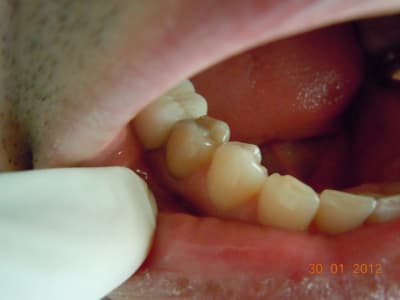

eMax de ce soir.

Collage automordançant G-Cem.

Bah voilà un argument de plus pour la levée de l'opposabilité pour les composites. Alors ameli? Qu'est qui favorise le plus l'accès au soins? Cet onaly qui doit coûter entre 300 et 500€ ou un compo à 150€ qui, collé dans les même conditions, aurait un pronostic équivalent?

(Il ne s'agit pas d'une critique de confrère, je prèfère cent fois quelqu'un qui soigne une carie comme ça qu'un autre qui foule 2 couches de compo sans digue)

Je trouve que c'est un patient qui devrait avoir des soins paro et des compo, pas des e-max. Et j'aime pas le collage au G-cem, en fait c'est le point faible de ton traitement, et c'est si facile de coller ce cas avec le total etch.

On peut penser qu'Arnaud aura vu le tartre sous-gingival et fait le nécessaire, mais pourquoi pas d'emax et plutôt des compos? Rapport à la taille des cavités? A l'hygiène pas top?

Oui rapport à la taille de la cavité. J'ai pas dit que c'était moins bien de faire un emax plutôt qu'un compo, je dis juste que c'est plus coûteux pour un bénéfice médical proche de zéro. Mais évidement si on veut faire un compo qui peut rivaliser avec cet onlay il faudra palper un pru plus que 28,92.

Il y a une équivalence thérapeutique entre les deux solutions tant que la forme de la préparation ne nécessite pas de délabrement, et bien que l'arsenal à mettre en œuvre est bien plus important pour l'inlay, je préfère de l'eMax dans ma bouche (et un peu de joint résine) qu'un compo.

Donc je choisis la solution où le patient est aussi bien soigné et où je ne sors pas du pognon de ma poche quand je le soigne.